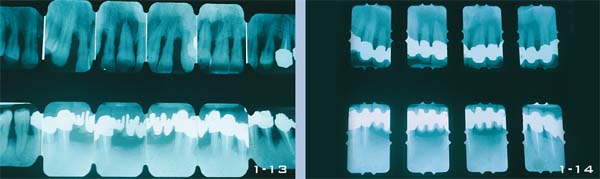

Abb. 1-10 bis 1-12 Ein vollständiger Röntgenstatus dient zur Diagnostik vor einer komplexen Behandlung und nach deren Abschluss. Diese Röntgenbilder zeigen die Situation zu Beginn, nach der ersten Präparation und unmittelbar nach Abschluss der Behandlung. Die 50-jährige Patientin zeigt eine schwere Parodontalerkrankung mit Auffächerung der Frontzähne und Verlust einiger Seitenzähne durch Furkationsläsionen. Die Patientin erhielt eine resektive Parodontaltherapie mit nachfolgender kieferorthopädischer Behandlung, Implantation und restaurativer Behandlung. Die Abschlussröntgenbilder zeigen die durch den kieferorthopädischen Eingriff intrudierten Oberkieferfrontzähne (Abb. 1-12).

Abb. 1-13 und 1-14 Vergleich des Röntgenbefundes der Frontzähne vor und nach der prothetischen Behandlung. Zustand nach Abschluss der orthodontischen Intrusion vitaler Zähne, präpariert zur Aufnahme von Kronen. Ziel war es, die Zähne zu verblocken und damit zu stabilisieren, um so ein Rezidiv der Protrusion der Zähne zu verhindern.